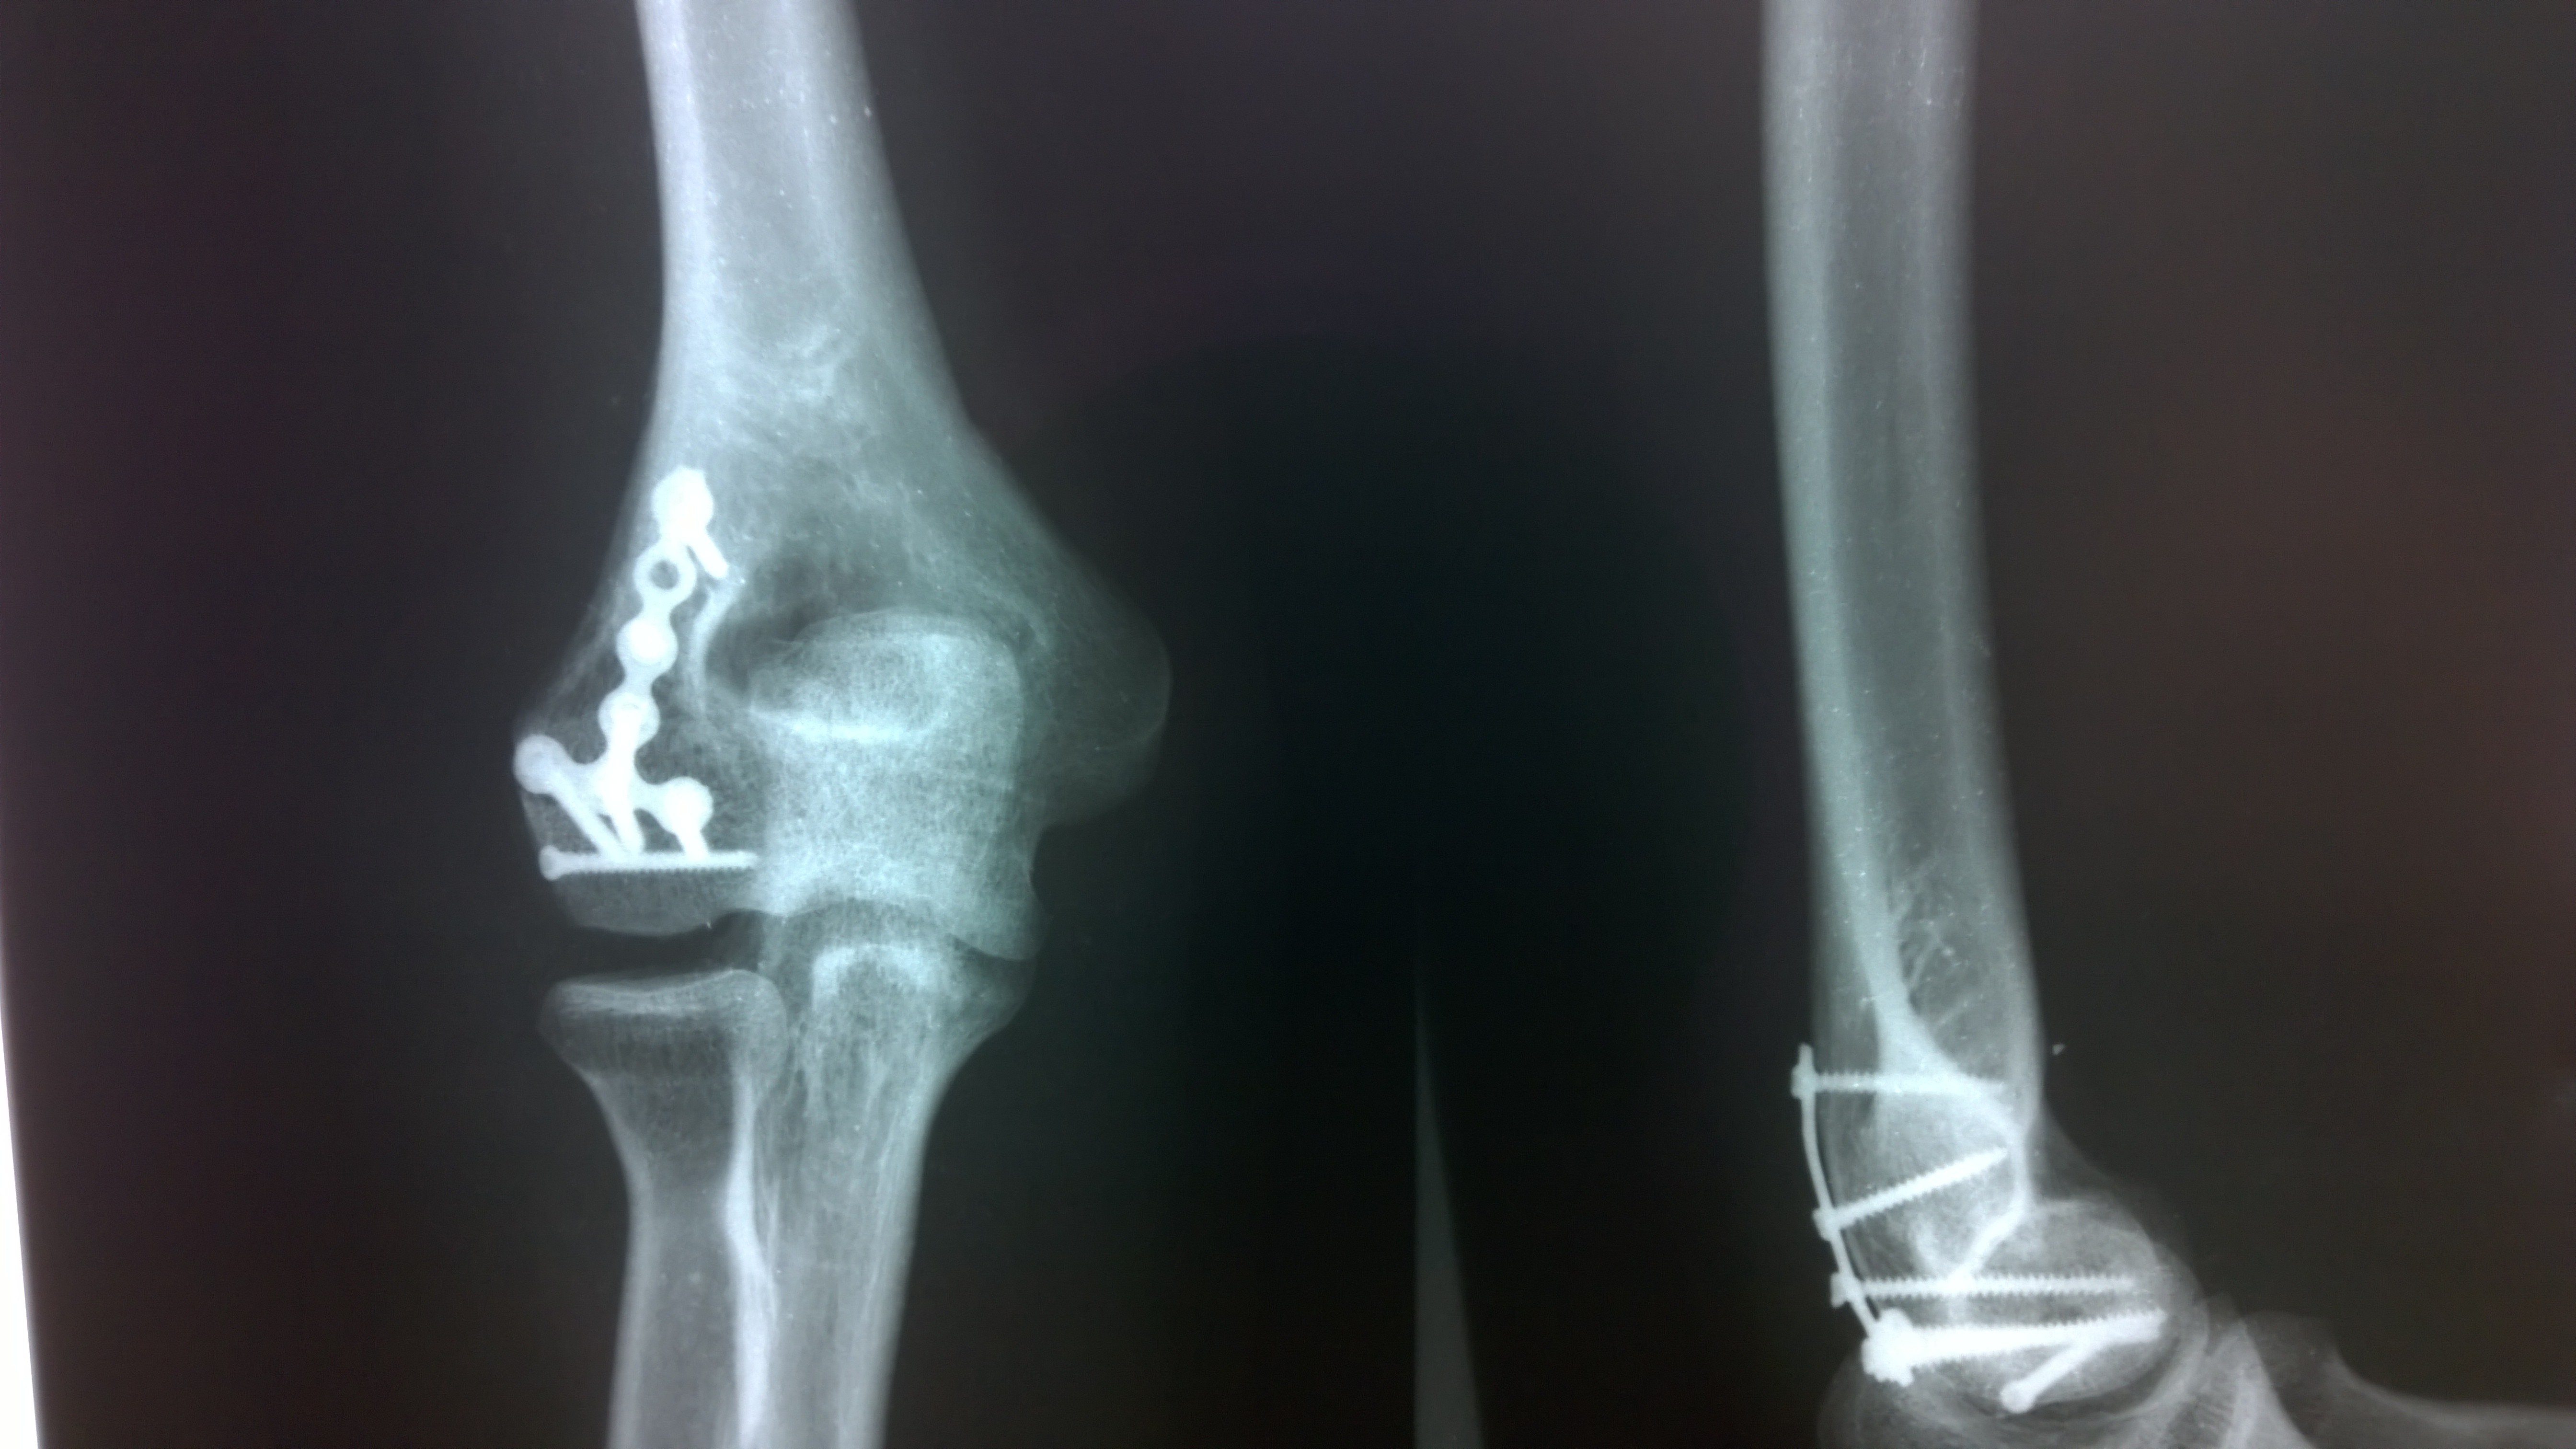

Закрытый перелом мыщелка плечевой кости